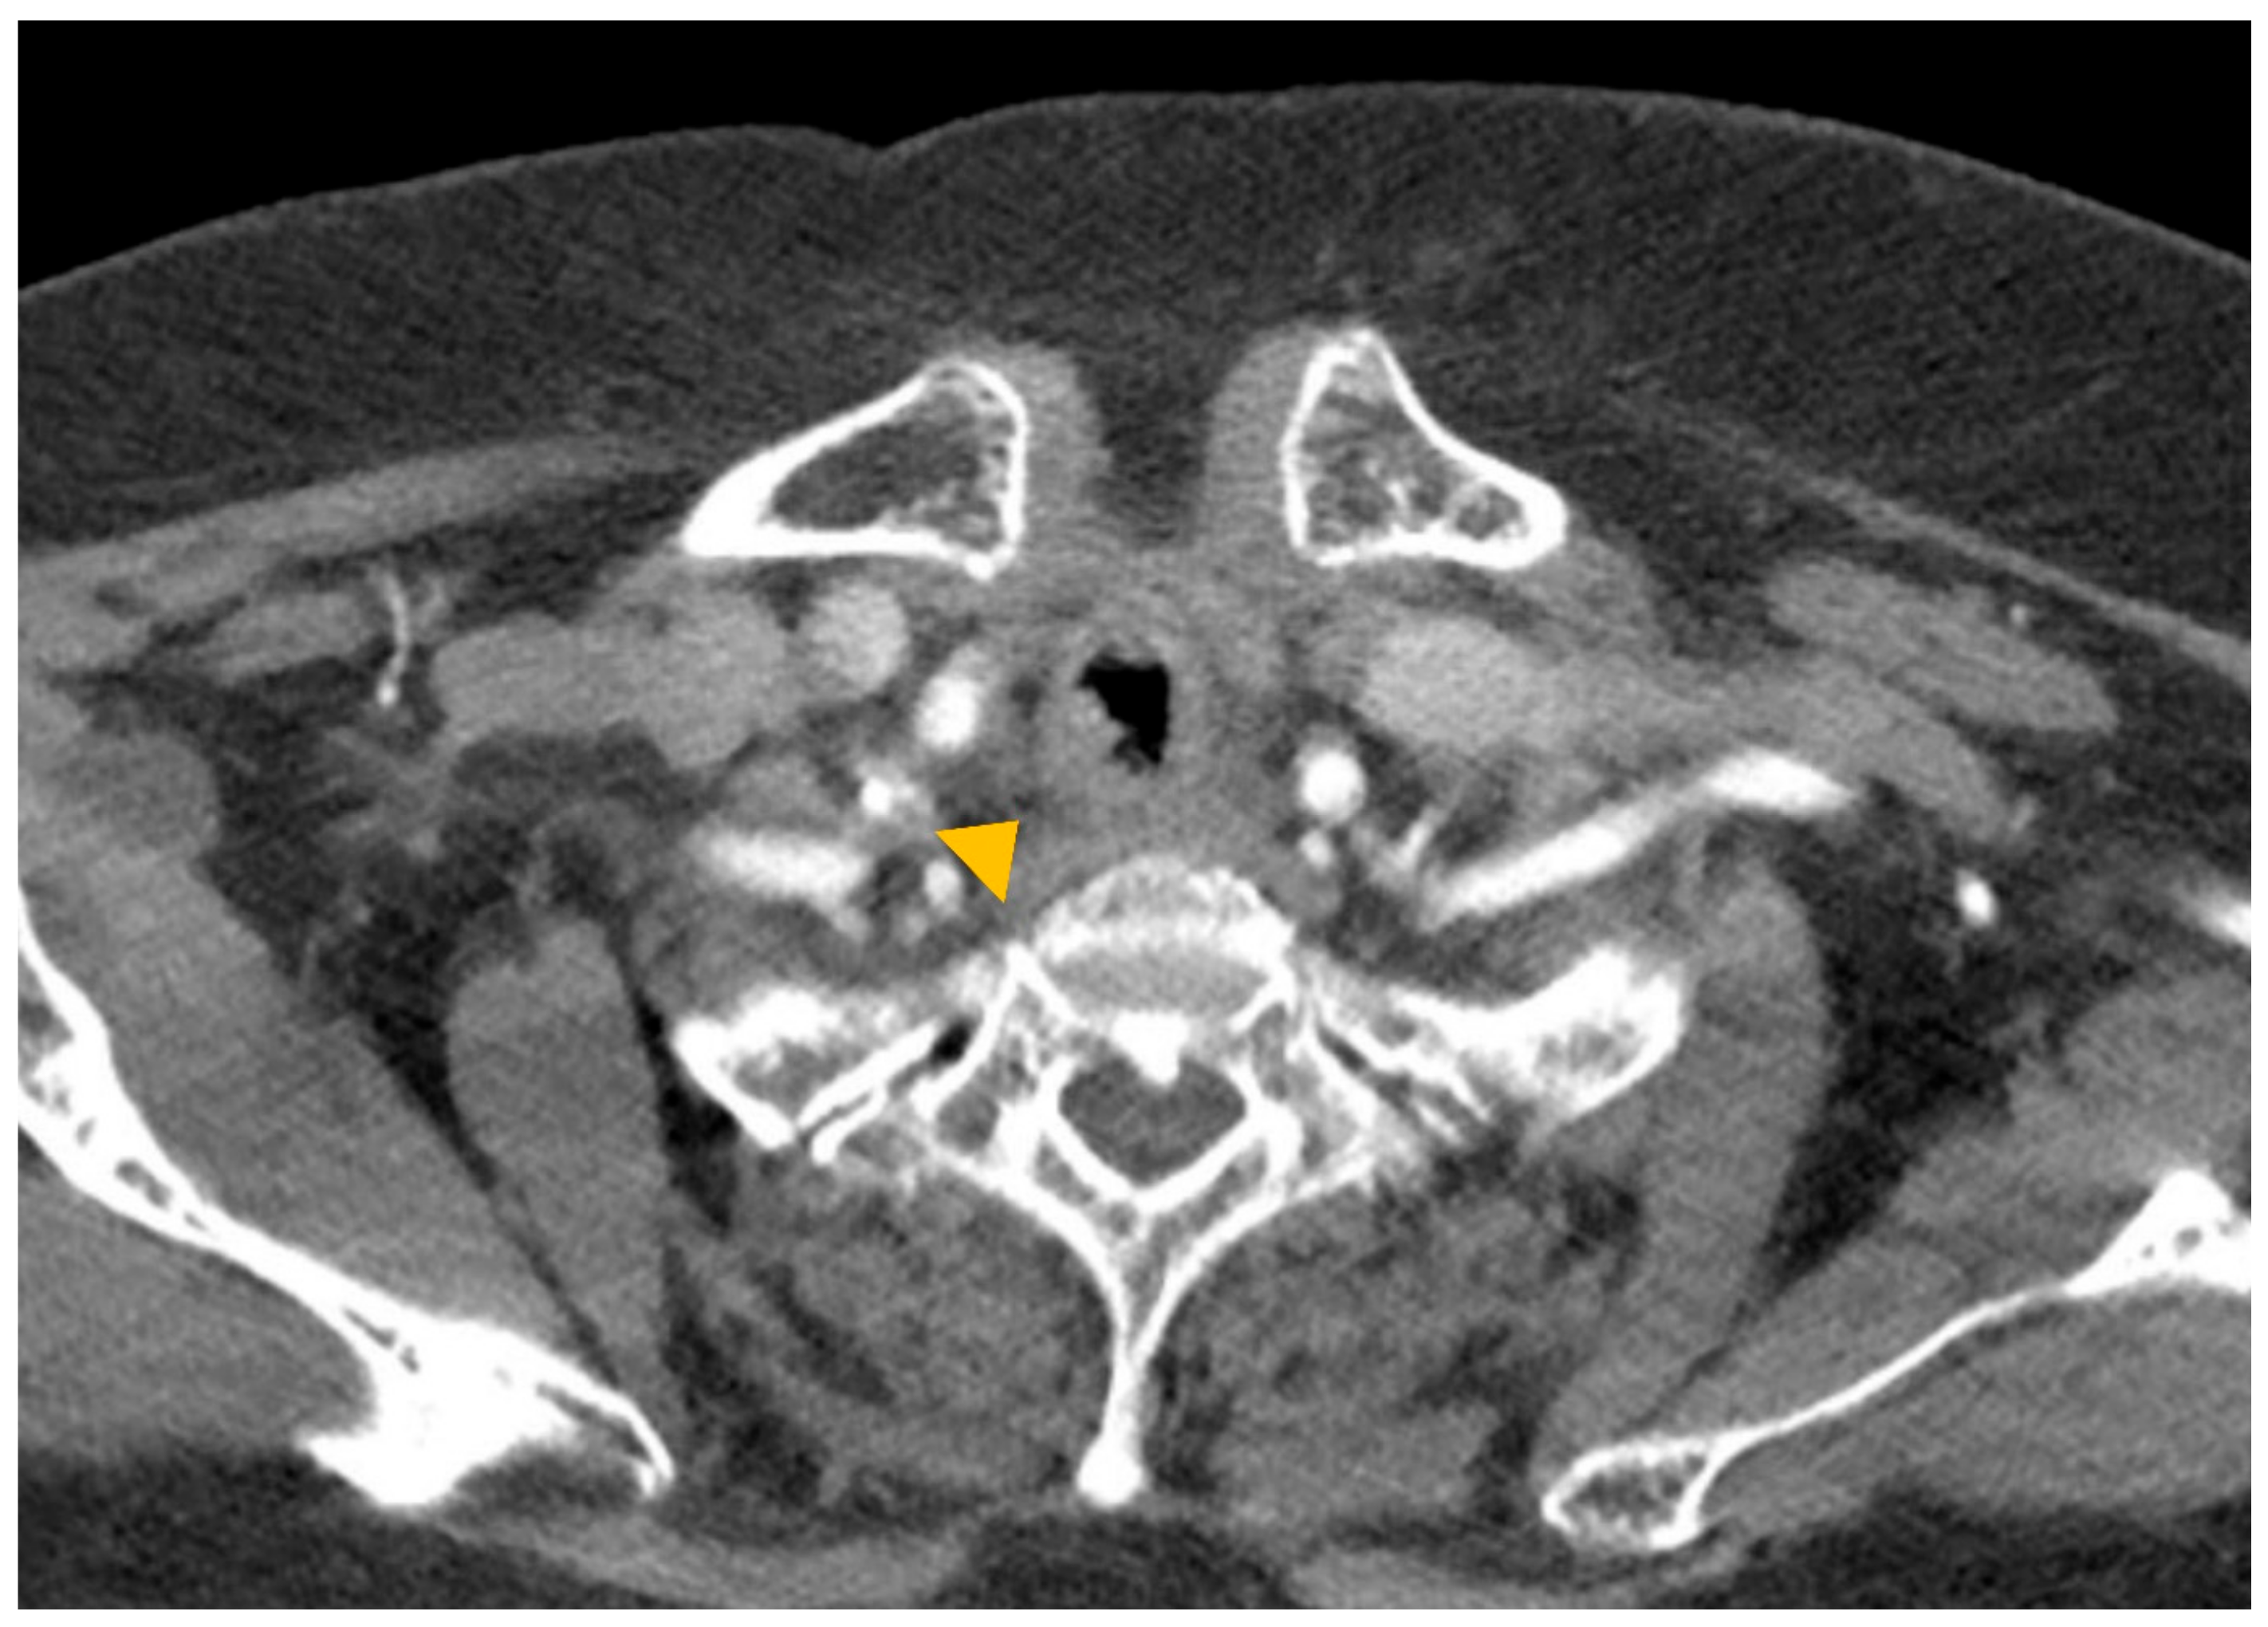

Tracheitis Caused by Coinfection with Cytomegalovirus and Herpes Simplex Virus

2. Case Report